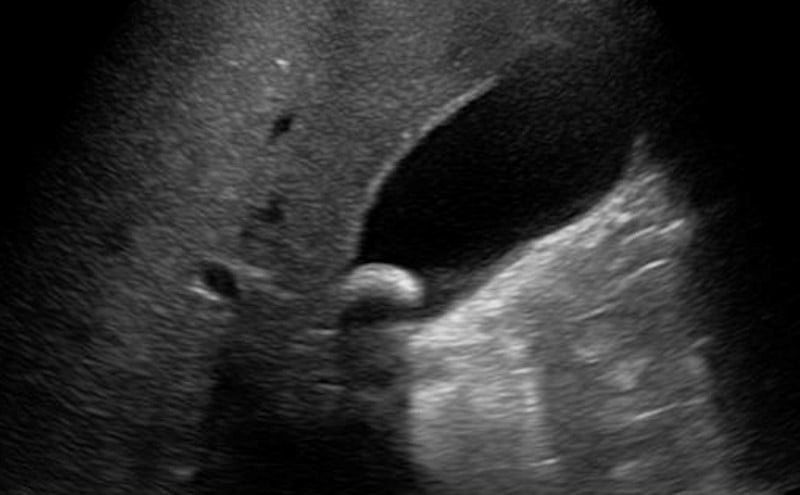

• The normal GB is pear-shaped, hypoechoic with a hyperechoic wall.

• Gallbladder long axis: Fan through the entirety of the gallbladder to identify any pathology (See Video 5 above: Long-axis of the gallbladder).

• Gallbladder short axis (See Video 6 above: Gallbladder short-axis): Rotate the probe 90 degrees. The GB will appear round. Again, fan through the entire GB.